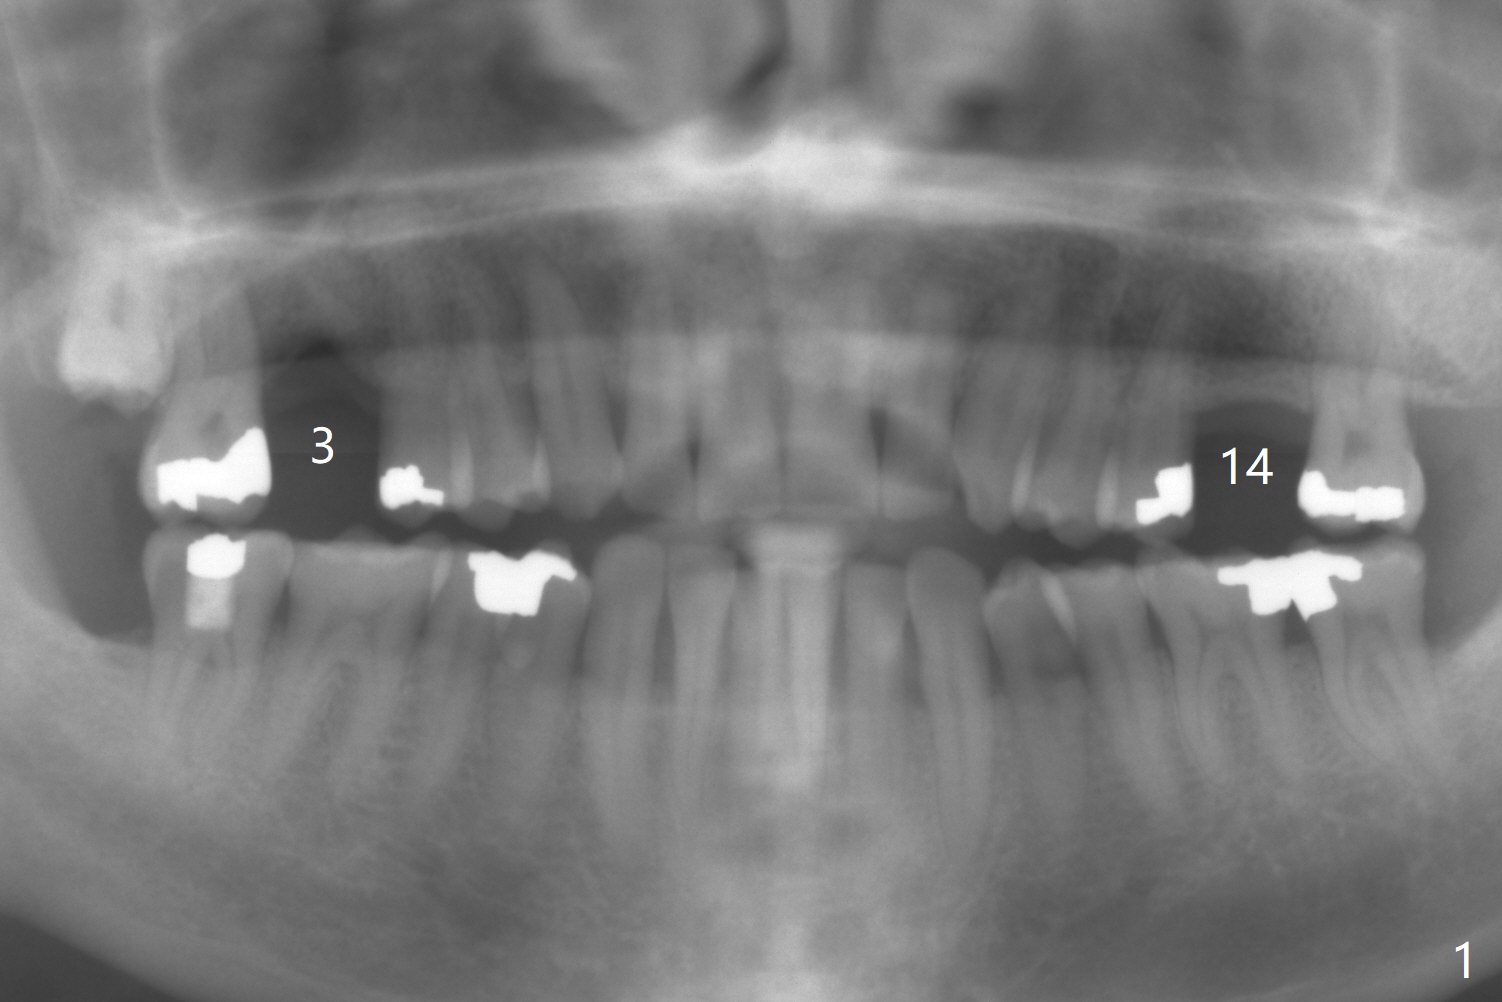

A 58-year-old man had 2 missing molar 3 years ago (Fig.1). Later the tooth #2 fractures with apparently severe bone loss (Fig.2). If the septum is lost, bone height is around 3 mm (Fig.3). Take PA before using Magic Sinus Lifter. Since his bone density is high, increase exposure time. If the septum is present (Fig.4), use Magic Drills sequentially (1.6, 2.8, 3.2 mm ....). PRF plug and membrane (1 each) are to be prepared.